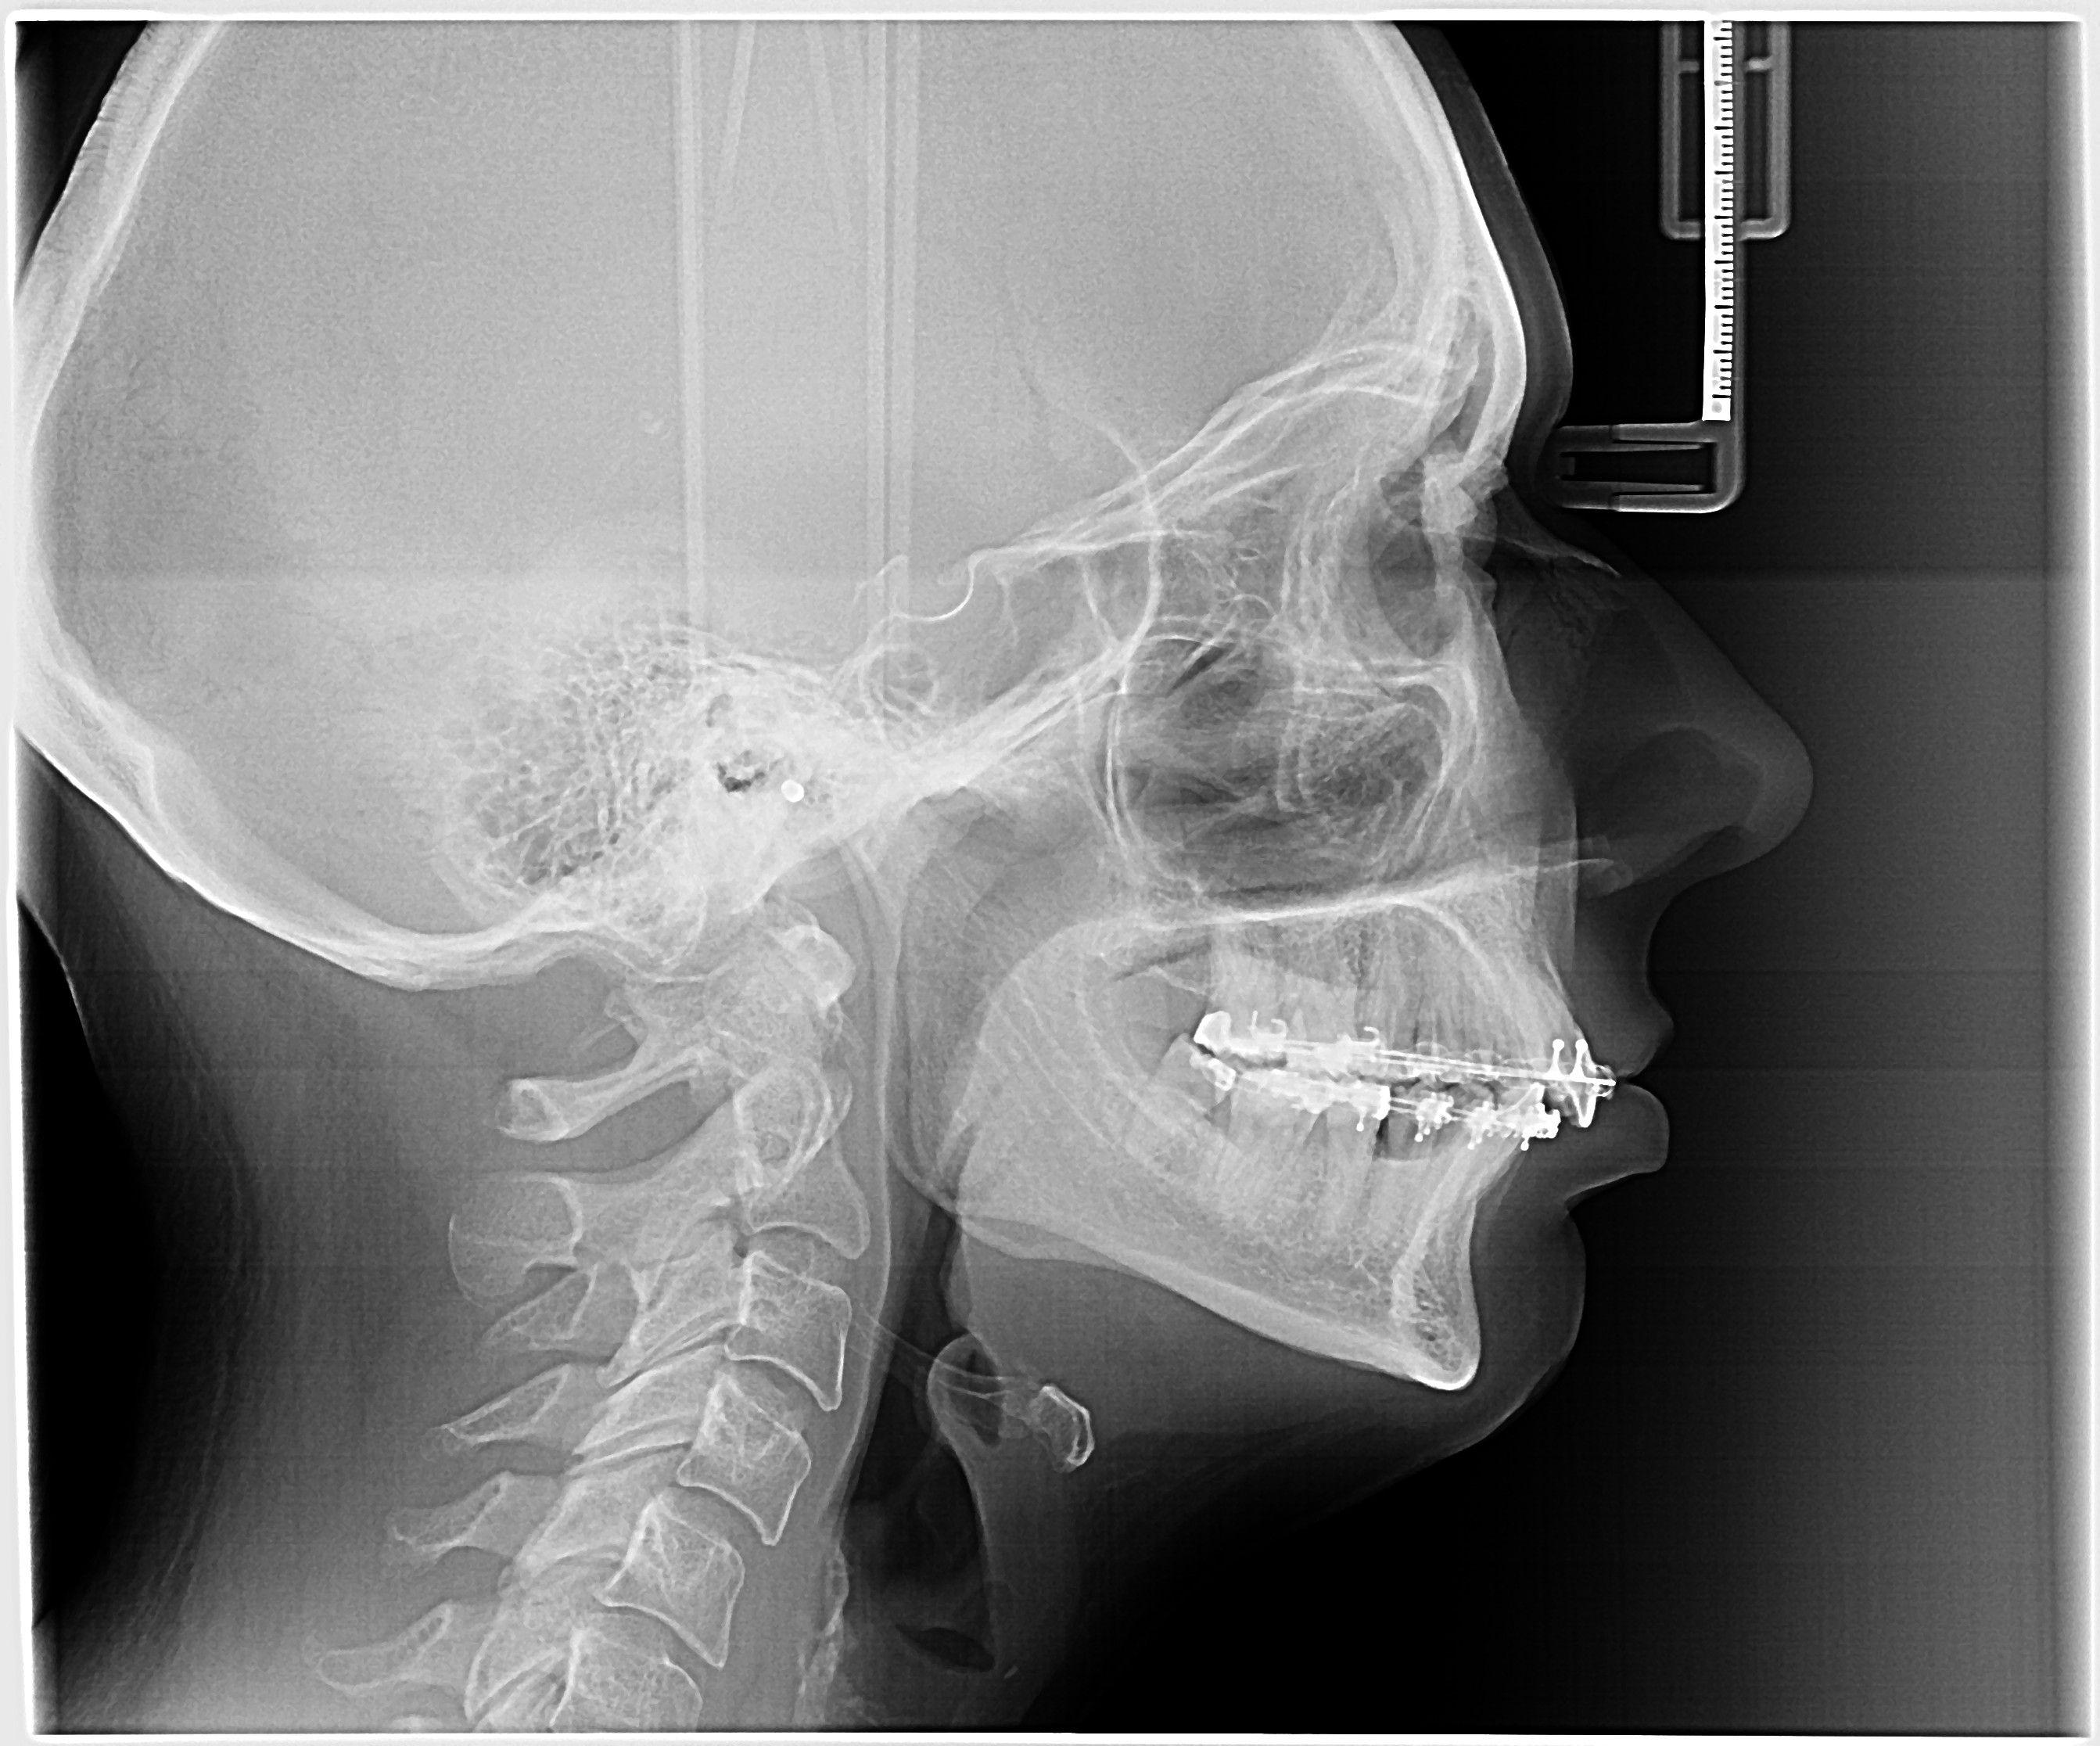

An advanced clinical assessment and decision-support tool for orthognathic surgery planning, enabling practitioners to analyze cephalometric measurements, classify skeletal patterns, and generate data-driven surgical treatment strategies.